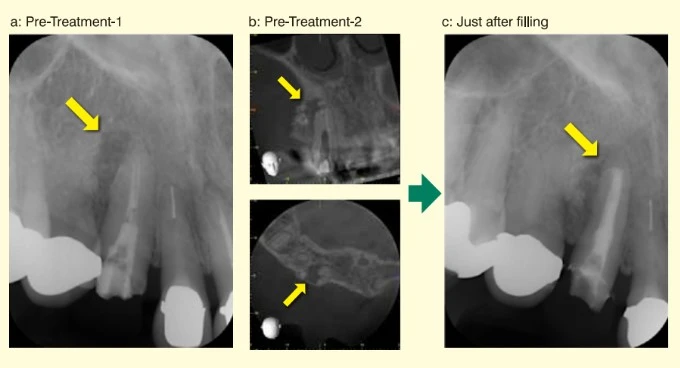

Hình ảnh tiền xử lý cho thấy một tổn thương lớn quanh chóp chân răng và tiêu chóp chân răng (Hình a và b, mũi tên).

Hình c cho thấy ảnh chụp xquang ngay sau khi trám bít ống tủy bằng BG Multi với kỹ thuật hình nón đơn. Quan sát trên phim ta có thể thấy vật liệu BG Multi đã tràn vào vùng hấp thu tại khu vực chóp răng.